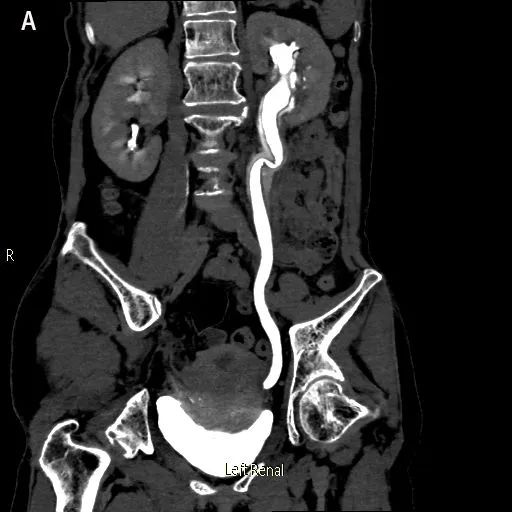

图4A

图4B

图4C

图4A-C:左侧肾盂及输尿管上段呈“双环及双腔样”改变,考虑夹层形成;三维重建可清楚的观察到撕裂肾盂及输尿管的真假腔并显示撕裂范围。